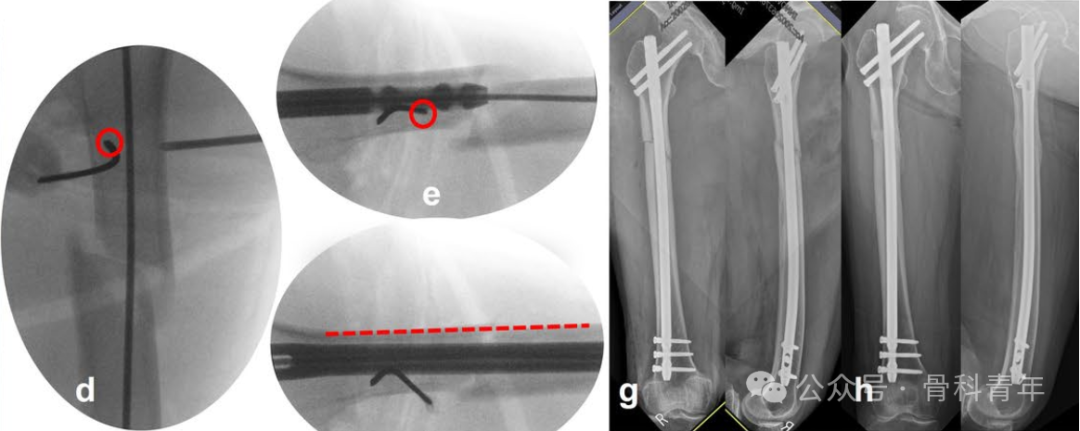

指征3:在侧位上,存在向前成角。除在冠状面的成角外,矢状面上的移位可以在侧位上体现。近端骨块在髂腰肌和外展肌群的牵拉下,容易向前成角。此时,需要将阻挡钉置于髓内钉前进方向的后方,纠正向前成角。

指征2:导针进针点准确,粗隆下内侧皮质粉碎,导致内翻畸形。粗隆下内侧皮质粉碎,失去对髓内钉的阻挡作用,导致近端骨块内翻。因此在术中,应在小粗隆水平髓内钉通道位置的内侧置入阻挡钉,纠正内翻。

指征1:导针进针点位于大转子外侧。由于近端骨块在肌肉牵拉下出现内翻、内旋畸形,术中精准置入导针比较困难。如术中导针置入大转子间外侧,则近端骨块会出现内翻畸形,此时,需将导针进针点开口扩大,留出髓内钉内移空间,后在髓内钉可能置入方向的外侧,置入阻挡钉,纠正内翻畸形。